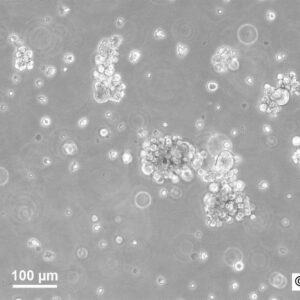

Morphology: Epithelial-like

Growth Properties: Adherent

Description: HuH7 was established in 1982 by Nakabayashi et al. from a 57-year-old Japanese male with well differentiated hepatocellular carcinoma.